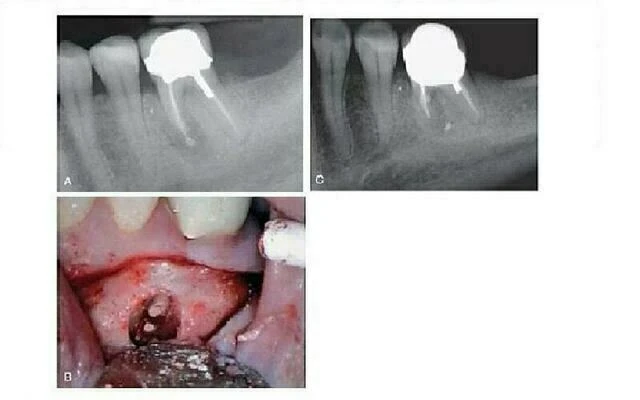

Hình 3. Nhiễm trùng tuỷ răng tái phát sau điều trị nội nha có thể là do nứt dọc chân răng